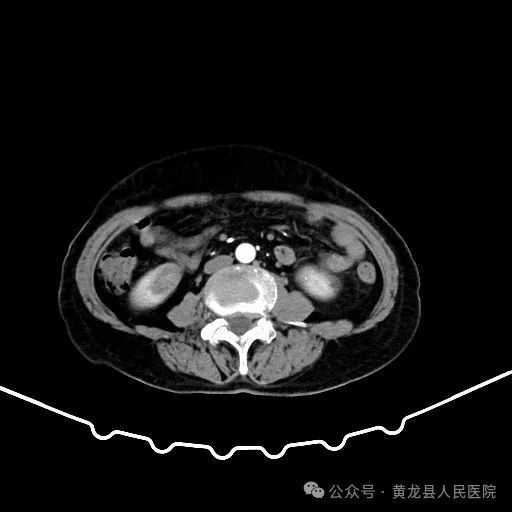

双肾增强CT

患者男性,70岁,因“发现右肾肿物1年余”收住于我院外科,经查体及相关检查后诊断为:右肾肿瘤。为尽早解除患者疾病困扰,方继荣主任迅速组织泌尿外科、手麻科、普外科等多学科进行会诊,对患者的病情进行了全面而深入的评估。最终确定详细周密手术方案,将患者病情及治疗方法告知患者及家属征得同意后,由我院泌尿外科刘涛主治医师实施手术。